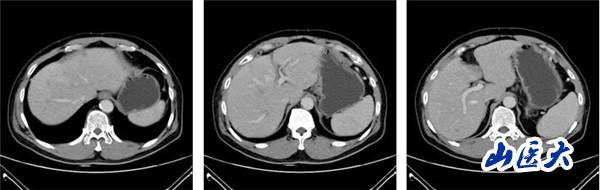

(2022-08-26复查肝脏CT静脉期)

该患者在团队成员仔细阅片、认真讨论下,因患者为PD-L1 CPS高表达人群,TMB-H基因状态。尽管目前国内外胰腺癌诊疗指南并没有对该类型患者指明个体化治疗策略,但通过查阅近年来已经报道的小样本临床研究以及个案报道资料,最终为患者制定了免疫联合化疗治疗策略:PD-1单抗+AG治疗6周期后,PD-1单抗+卡培他滨维持治疗。2022年8月26日,患者再次完善胸腹部CT评价疗效后,达到了大PR(部分缓解)的效果。多达20余处肝转移病灶几乎消失不见,患者可以正常工作生活。